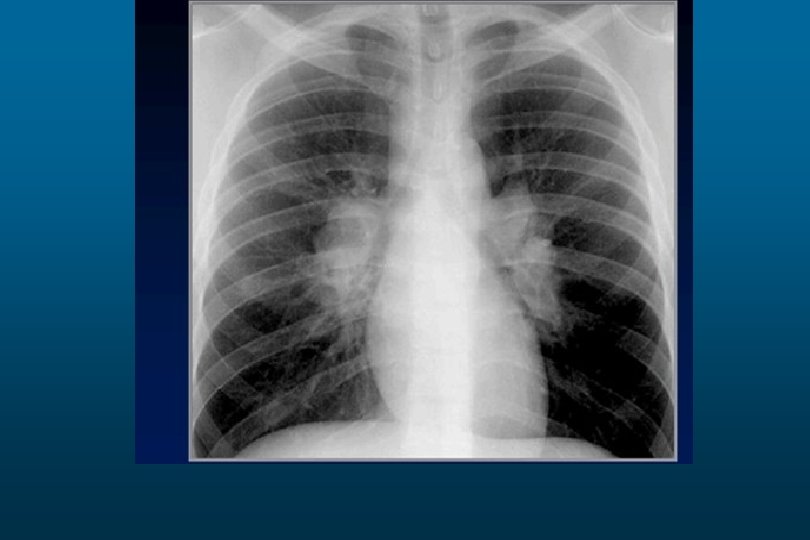

Large pleural effusion